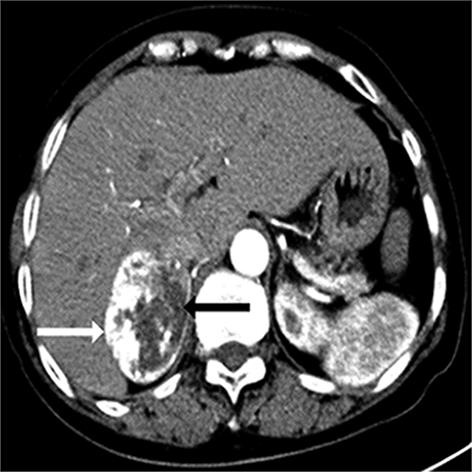

• 嗜铬细胞瘤及副神经节瘤不同生化表型的CT征象对比研究

2024, 49(2):203-209. DOI: 10.13406/j.cnki.cyxb.003433

摘要 (51) HTML (33) PDF 3.10 M (96) 评论 (0) 收藏

摘要:目的 分析生化阴性嗜铬细胞瘤及副神经节瘤(pheochromocytomas and paragangliomas,PPGLs)的电子计算机断层扫描(computed tomography,CT)征象是否有别于生化阳性PPGLs,同时了解生化阳性PPGLs不同表型的CT征象是否存在差异。方法 回顾性分析131例PPGLs患者的术前腹部增强CT图像,包括肿瘤位置、大小、形态、囊变坏死、液-液分层、钙化、向心结节状强化、肿瘤内粗大血管、强化包膜、绝对廓清率及相对廓清率。根据生化水平,将患者分为生化阳性组和阴性组,阳性组进一步分为去甲肾上腺素型、肾上腺素型及多巴胺型。比较各组及各表型间的CT征象差异。结果 相较于生化阴性组,阳性组PPGLs更大(Z=-2.064,P=0.039)、囊变坏死(χ2=6.610,P=0.010)及向心结节状强化(χ2=3.909,P=0.048)的比例更高;相较于去甲肾上腺素型,肾上腺素型PPGLs更大(Z=-2.036,P=0.042)、强化包膜比例更高(χ2=7.242,P=0.007)。结论 肿瘤大小、囊变坏死及向心结节状强化的CT征象有助于术前诊断生化阴性PPGLs,肿瘤大小及强化包膜有助于解释去甲肾上腺素型及肾上腺素型PPGLs不同临床表现产生的机制。